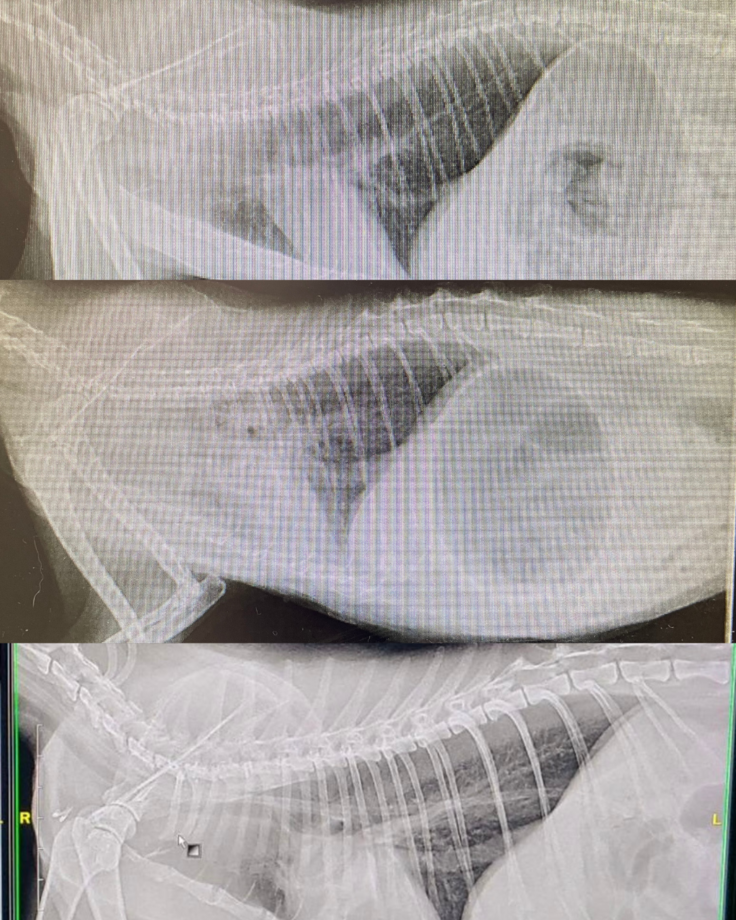

▼レントゲン画像

上から、最初の通院時、入院時、退院時の比較です。

左側の白いモヤモヤが炎症です。

退院時の画像では、モヤモヤがひいたので骨がくっきり映っているのがわかります。